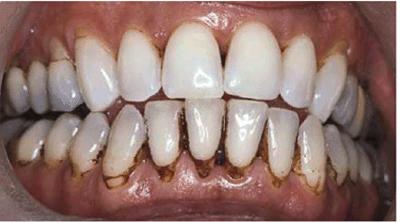

either on an individual tooth or on all teeth (Figures 16-1A, and 16-1B). There are many causes and

Figure 16-1A: An otherwise attractive smile is marred by discolored teeth.

Figure 16-1B: After tooth lightening, the smile is much more pleasing.